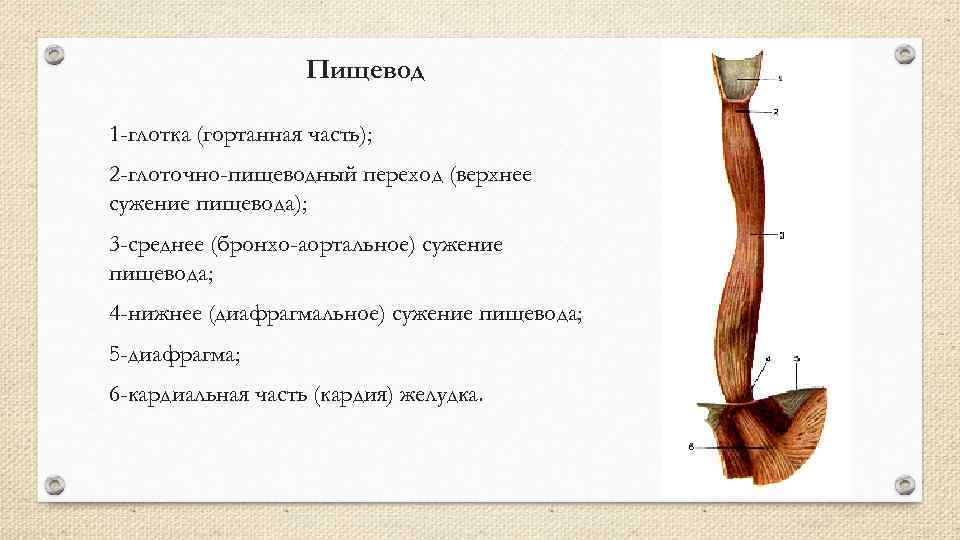

Пищевод 1 -глотка (гортанная часть); 2 -глоточно-пищеводный переход (верхнее сужение пищевода); 3 -среднее (бронхо-аортальное) сужение пищевода; 4 -нижнее (диафрагмальное) сужение пищевода; 5 -диафрагма; 6 -кардиальная часть (кардия) желудка.

Пищевод 1 -глотка (гортанная часть); 2 -глоточно-пищеводный переход (верхнее сужение пищевода); 3 -среднее (бронхо-аортальное) сужение пищевода; 4 -нижнее (диафрагмальное) сужение пищевода; 5 -диафрагма; 6 -кардиальная часть (кардия) желудка.